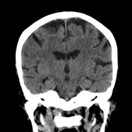

History of Ischemic Stroke

2 years ago. Diagnosed as a left middle cerebral artery (MCA) lacunar infarct.

• Sequelae: Mild, persistent weakness in his left leg. He walks with a slight limp but is fully independent and ambulatory, with no residual arm or speech deficits.

• Previous CT-scan: